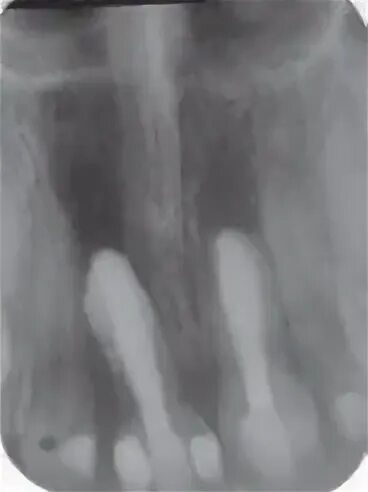

Признаки резорбции